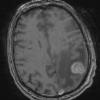

NEOPLASMS (METASTASES)